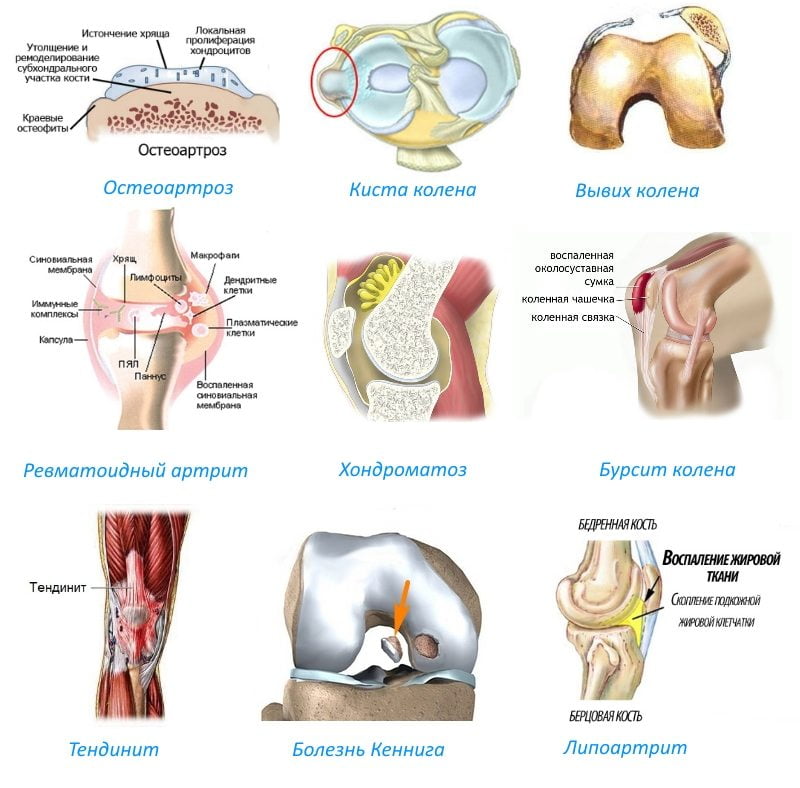

Нередко термины артроз и артрит путают, а также называют артрозо-артритом. Но эти термины имеют принципиально разное значение и разные заболевания. Объединяет их корень(artron) — означающий сустав. Артрит это воспалительное заболевание сустава (суставов) и воспалительный процесс, так или иначе, воздействует на другие органы и системы всего организма вследствие аутоиммунных (например, ревматологические заболевания, такие как ревматоидный артрит, СКВ) или других нарушений. При обменных нарушениях (например, при подагре или сахарном диабете) поражаются суставы и, в таких случаях применяется термин артропатия. Термин артралгия используется для обозначения болей в суставах различного генеза. Артрозы же или остеоартрозы обозначают дегенеративные изменения в суставах, возникающие в возрасте старше 45-50 лет вследствие естественного износа. Таким образом, принципиальной разницей между артритом и артрозом является то, что артрит воспалительное заболевание, в то время как артроз это дегенеративные изменения в хряще вследствие инволюционных изменений в организме и естественного износа хрящевой ткани суставов.

По сравнению с артритом, это заболевание не является воспалительное заболеванием суставов. Тем не менее, происходит повреждение суставного хряща. Причиной могут быть как инволюционные изменения, так и травмы или износ хрящевой ткани вследствие избыточных нагрузок. Артроз может проявляться отеком и болью. Также в некоторых случаях заболевание может приводить к изменениям в других органах и системах. Оно может приводить как снижению объема движений, так и амплитуды движений. Чаще всего, артроз поражает бедренные суставы, коленные суставы, суставы позвоночника. Артроз, нечасто используемый термин для описания дегенеративных заболеваний суставов. Для понимания важно сначала понять анатомию сустава. Концы костей, которые формируют сустав, имеют гладкую поверхность, которая называется субхондральной частью кости. За ней находится суставной хрящ, который является прочной, но эластичной соединительной тканью и благодаря этому защищает кости, облегчает движение между поверхностями, а также действует как амортизатор.

Остеоартрит развивается тогда, когда изнашивается хрящ, покрывающий суставные поверхности, обычно опорных суставов — колена или бедра. Тогда избыточная жидкость накапливается в суставе, вызывая припухлость, боль и ограничивая его подвижность.

Ревматоидный артрит вызывается воспалением соединительной ткани суставов, а иногда также и хряща. Пораженные суставы опухают, становятся малоподвижными и болезненными. При этой форме артрита нормальная реакция иммунной системы организма обращается против соединительной ткани сустава. Первые признаки проявляются на суставах пальцев рук, запястий и пальцев ног. Предрасположенность к ревматоидному артриту может быть наследственной, а роль пускового механизма играют различные факторы. Это заболевание обычно сопровождается усталостью, анемией, плохим кровообращением и болезнями сухожилий, глаз и щитовидной железы.

Остеоартрит – воспалительный артрит, развивающийся сравнительно медленно, в течение нескольких месяцев или лет. Чаще всего остеоартрит поражает коленные суставы, тазобедренный сустав и суставы кисти.

Ревматоидный артрит – это разновидность воспалительного артрита, к которому также относятся подагра и воспалительный артрит. Ревматоидный артрит представляет собой хроническое заболевание соединительных тканей, имеет аутоиммунную природу и поражает преимущественно мелкие суставы, например, суставы кисти.

- Остеоартрит, болезнь износа, является наиболее распространенным типом артрита.

- Ревматоидный артрит — это аутоиммунное заболевание, которое возникает, когда ваше тело атакует собственные ткани.

- Бурсит — это воспаление мешочков с жидкостью, которые помогают смягчить суставы.

- Подагра — это форма артрита, которая чаще всего поражает сустав большого пальца ноги.